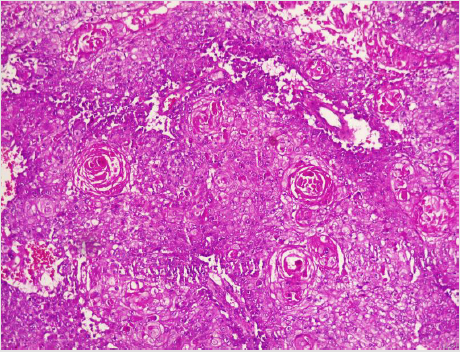

A diagnostic breast USS with a 5 MHz probe was done. A thickwalled 12 cm cystic lesion with multiple septations was seen. It has a 3 cm solid component, with no calcification or increased flow on Doppler interrogation. A fine needle aspiration was done, about 60 mls of straw-coloured fluid was drained and cytological analysis of the aspirate showed suspicious ductal cells. A wide local excision with axillary dissection and immediate breast reconstruction was done. Histopathological analysis showed malignant squamous epithelial cells that are disposed in sheets and nests with focal areas of keratin pearls (Figure 1A). The cells are polygonal with intercellular bridges (Figure 2B). Immunohistochemical staining with HMW Cytokeratin Antibody was positive. Immunohistochemical staining for focal Carcino-embryonic-antigen and E-cadherin was negative. The resection and deep margins are free of tumour and only the enlarged lymph node showed metastatic deposit. No adjuvant chemotherapy or radiotherapy given. Immunohistochemical study of molecular profile showed positivity for oestrogen only, progesterone receptor was negative and there is no over expression of the Her2-Neu receptor. Patient is currently on adjuvant selective oestrogen receptor modulator (Tamoxifen) at 20 mg daily for a two and a half years and will be subsequently switched to an Aromatase inhibitor {Anastrazole) for the same duration. Patient is to continue with follow-up visits to the surgical-out-patient-department. An informed consent was obtained from the patient for publication of the case report.

Figure 1: Photomicrographs of malignant squamous epithelial neoplasm that are disposed in sheets with focal areas of keratin pearls (A), A=X100.

A diagnostic breast USS with a 5 MHz probe was done. A thickwalled 12 cm cystic lesion with multiple septations was seen. It has a 3 cm solid component, with no calcification or increased flow on Doppler interrogation. Other authors have reported also that there are no typical findings on the mammogram and a breast USS may only reveal a complex cystic mass with solid component or an inflammatory process [42]. Calcification and Cystic changes are often the frequent radiological finding [24-26,58]. A fine needle aspiration was done, about 60 mls of straw-coloured fluid was drained and cytological analysis of the aspirate showed suspicious ductal cells. A Tru-cut biopsy is the preferred method of obtaining a pathological diagnosis, as fine needle aspiration study is often not helpful [42]. In a study done by Gupta RK et al, very few patients have the histological diagnosis confirmed via a fine needle aspiration [62,63]. A wide local excision with axillary dissection and immediate breast reconstruction was done. Histopathological analysis showed malignant squamous epithelial neoplasm that are disposed in sheets and nests with focal areas of keratin pearls (Figure 1A). The cells are polygonal with intercellular bridges (Figure 2B). The reported histological evidence of a primary SCC of the breast is the microscopic appearance of malignant cells composed of infiltrative nests of atypical epithelial cells with irregular and hyperchromatic nuclei. There may be variable amounts of keratinous lamellar or a pseudo-sarcomatoid stroma [64-68]. It may have associated Ductal Carcinoma In-Situ or squamous metaplasia of ductal epithelium at the periphery of the invasive carcinoma [23,25,26,59,69]. Immunohistochemical staining with HMW Cytokeratin was positive. immunohistochemical staining for focal Carcinoembryonic- antigen and E-cadherin was negative. For adequate treatment, it is imperative to separate cutaneous SCC from primary SCC of the breast. Apart from the requirement of the predominance (>90%) of the squamous malignant cells in all the arrears of the tumour, the tumour should have no continuity with overlying epidermis or dermal appendages [31]. Immunohistochemical staining has emerged as an important diagnostic tool in making such distinction. Both the pure primary SCC of the breast and the SCC extending in to breast parenchyma from overlying skin stain positive with HMW-CK antibody. But, only primary pure SCC shows diffuse positive staining for CK 7, CK 8 and CK19 Antibodies [33- 36]. The distinction of pure primary SCC from secondary SCC from extra mammary sites such as the lungs is also difficult, because SCC differentiation demonstrate identical immunohistochemical staining in every organ in the body [21]. The demonstration of MAP2K4 gene mutation in a biopsied specimen should confirm an extra mammary origin, especially a lung SCC [21,70].